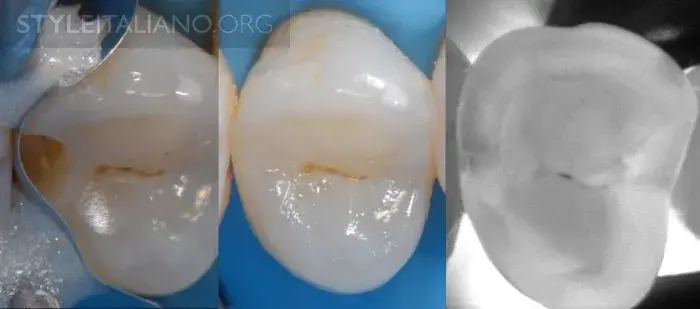

Рис. 12 – Восстановление зуба.

Рис. 15 — Предоперационный вид/ Лазерное просвечивание/ Рентген.

Рис. 16 – Просвечивание зубов показывает полости в истинном размере, а на рентгене они уменьшены.